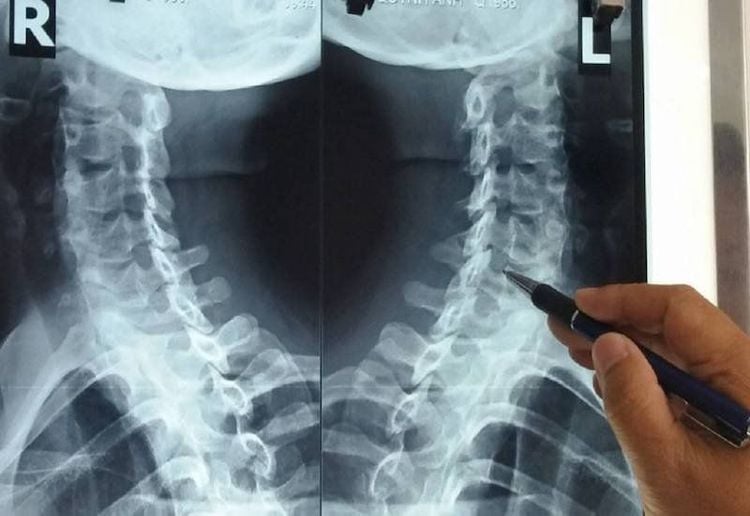

Ảnh minh hoạ